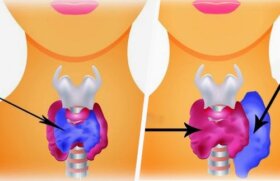

갑상선 이상 증상을 조기에 발견하는 것은 아주 중요하다.

우리는 갑상선 기능 저하증과 갑상선 기능 항진증, 이 두 가지 질병에 익숙하다. 하지만 이 두 질병이 어떤 차이가 있는지 알고…